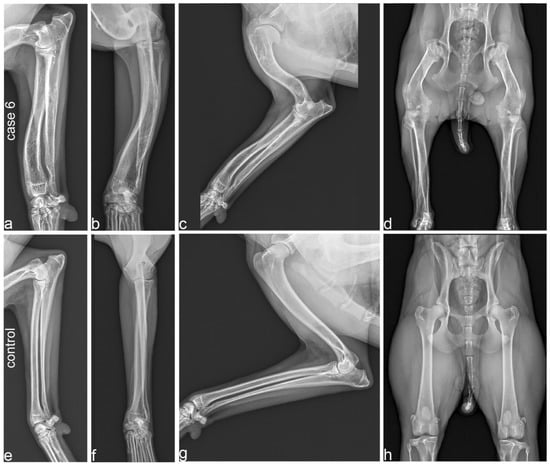

3.2. Diagnostic Imaging